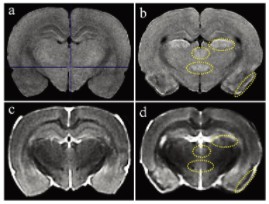

圖1顯示了T1和T2加權(quán)MRI圖像。與對照組相比, 匹羅卡品處理的動物在梨狀皮質(zhì)、丘腦外側(cè)核、丘腦室周后核和大腦下丘腦后核的T1加權(quán)圖像顯示出高T1信號(圖1a和b)。在匹羅卡品處理的動物的T2加權(quán)圖像中,與對照組相比,在梨狀皮質(zhì)觀察到低T2信號,對應(yīng)于高T1信號區(qū)(圖1c和d)。其他3個高T1信號區(qū)的T2信號強度與對照組相當(中等強度)(圖1c和d)。

當前易于使用的緊湊型小動物磁共振成像系統(tǒng)在匹羅卡品誘導(dǎo)的大鼠腦損傷的臨床前毒理學(xué)病理檢查中的適用性。高T1和低T2信號顯示明顯的組織病理學(xué)神經(jīng)元損傷,盡管組織病理學(xué)檢查更為敏感。